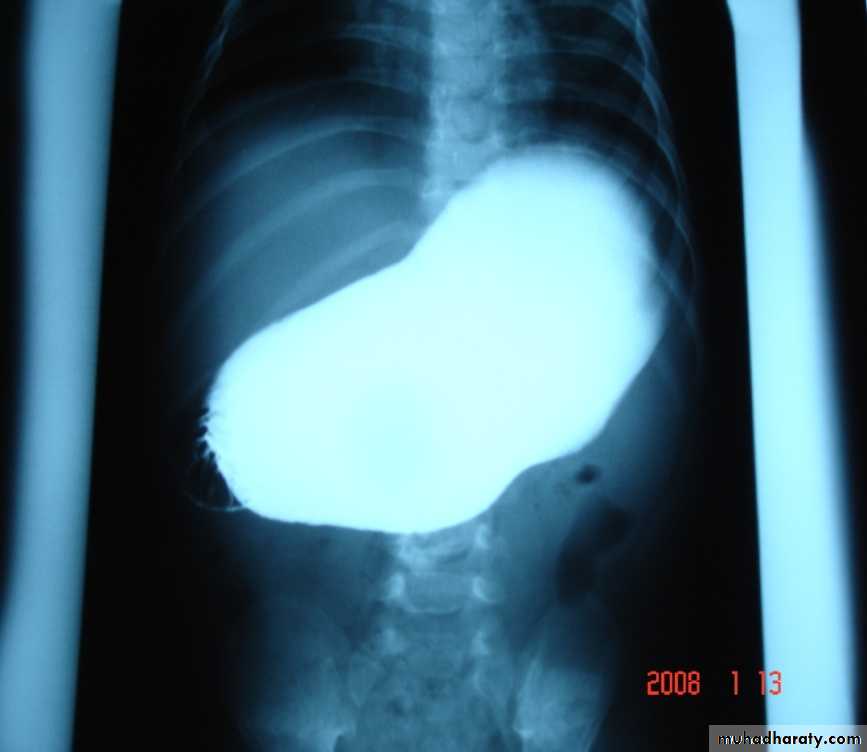

What is the differential diagnosis?Timing of operation?A 4 week old boy presents with vomiting. The pictures show the investigation and the operative findings.1. What is the diagnosis ?2. What is the investigation shown in slide A ?3. How do you treat ?4. What is the character and contents of vomitig in this pathology?5. What are the other methods of diagnosis?